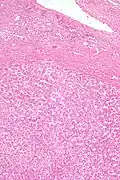

| Micrograph of a hepatic adenoma (bottom of image). H&E stain | |

Pathologic diagnosis

Hepatic adenomas are, typically, well-circumscribed nodules that consist of sheets of hepatocytes with a bubbly vacuolated cytoplasm. The hepatocytes are on a regular reticulin scaffold and less or equal to three cell thick.

The histologic diagnosis of hepatic adenomas can be aided by reticulin staining. In hepatic adenomas, the reticulin scaffold is preserved and hepatocytes do not form layers of four or more hepatocytes, as is seen in hepatocellular carcinoma.

Cells resemble normal hepatocytes and are traversed by blood vessels but lack portal tracts or central veins.

Micrograph of hepatic adenoma. H&E stain -